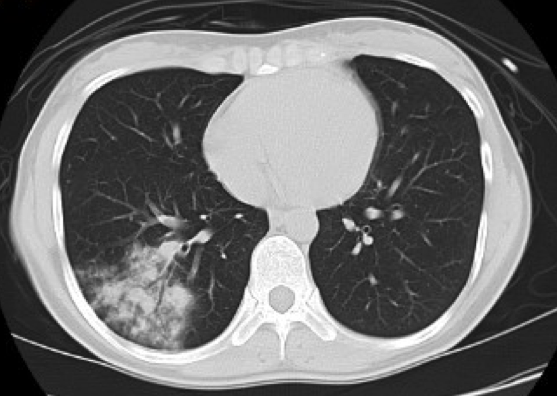

80列マルチスライス撮影により、撮影は約10秒程度です。また、被ばくに対し配慮した設計により、高感度のX線検出器を使用し、低線量、高画質の撮影で安心して検査を受けて頂く事が出来ます。